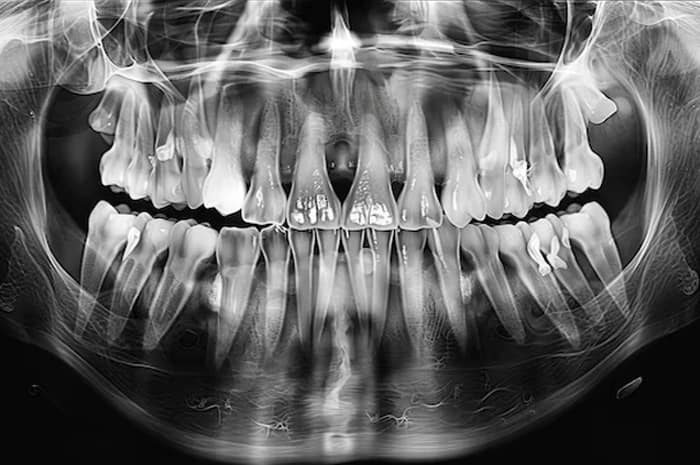

بهترین مرکز عکس دندان در رباط کریم | انتخاب هوشمند برای سلامت دندان

مقدمه داشتن دندانهایی سالم فقط به مسواکزدن و نخدندان محدود نمیشود؛ گاهی لازم است وضعیت درونی دندانها و استخوان فک بررسی شود تا مشکلات پنهان زودتر تشخیص داده شوند.در این میان، عکس دندان یکی از مهمترین ابزارهای تشخیص دندانپزشکی است. اگر در منطقه رباط کریم زندگی میکنید، دسترسی به یک مرکز معتبر برای عکس دندان […]

عکس دندان در پرند با دستگاه دیجیتال | تفاوت با رادیولوژی معمولی و OPG پرند

در دندانپزشکی مدرن، عکس دندان یکی از اصلیترین مراحل تشخیص و درمان است. اگر ساکن پرند یا رباط کریم باشید، احتمالاً عبارتهایی مثل «عکس دندان در پرند» یا «OPG پرند» را زیاد شنیدهاید.اما آیا میدانید عکس دیجیتال دندان چیست و چه تفاوتی با رادیولوژی معمولی دارد؟در این مقاله، همه چیز را به زبان ساده توضیح […]